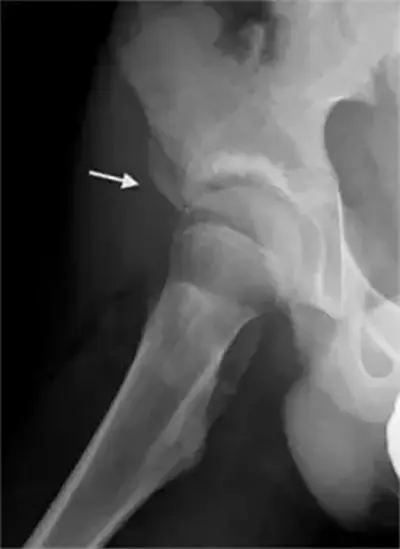

- X-rays: To detect bony overgrowth, structural abnormalities, or fractures